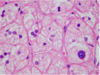

Normal Endocrine Pancreas